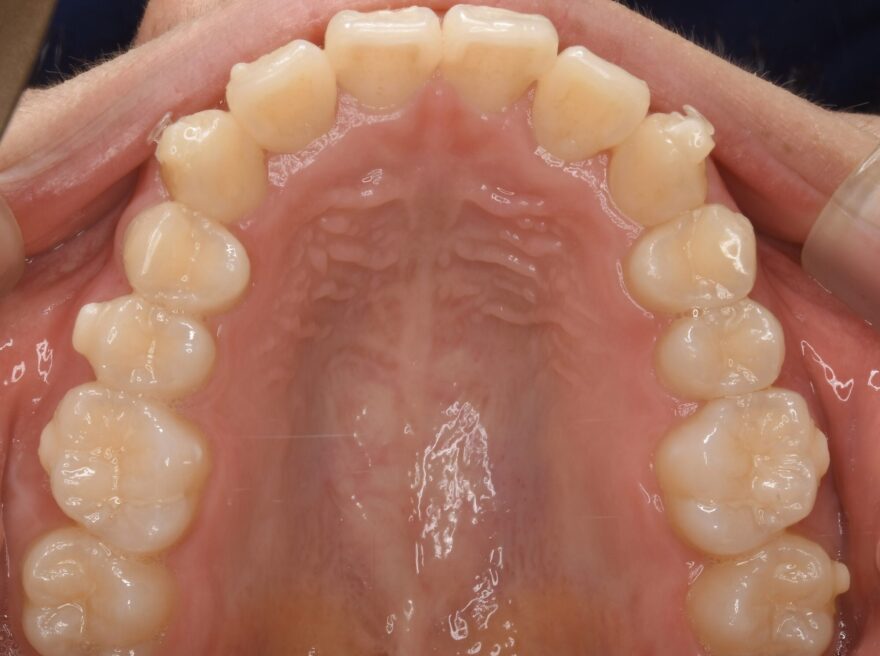

治療後の口腔内写真

約2年の動的期間(歯を動かす時期)で、ここまで整った歯並びになりました。

インビザラインでもワイヤー矯正でも、最終的な仕上がりに差はありません。

八重歯が完全に治りました。

前歯には後戻りを防止するための保定装置を装着しています。

下顎の前歯にもワイヤーによる保定装置を装着しています。